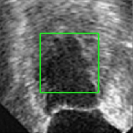

4.5 Comparison with breast ultrasound images segmentation

Unlike MR images mentioned above, ultrasound images offer real-time imaging but usually have lower resolution and contrast, making it difficult to differentiate between adjacent tissues and often introducing artifacts and noise that complicate segmentation. However, the RefLSM is robust to high levels of noise and intensity inhomogeneity, regardless of the type of medical image. To validate this, we perform segmentation comparison experiments on breast ultrasound images and calculate the Dice coefficient and Precision values for all models under evaluation.

In Fig. 10, the 1st row displays original images and initial contours for the RefLSM, while the second row shows the RefLSM’s segmentation results. Even with high levels of noise and severe intensity inhomogeneity caused by acoustic shadowing and motion artifacts, our model successfully identifies object edges, achieving an average Precision value of 0.9812. Table 4 shows that the RefLSM requires no more than 10 iterations and has an average processing time of only 1.79 seconds to segment images in Fig. 10.